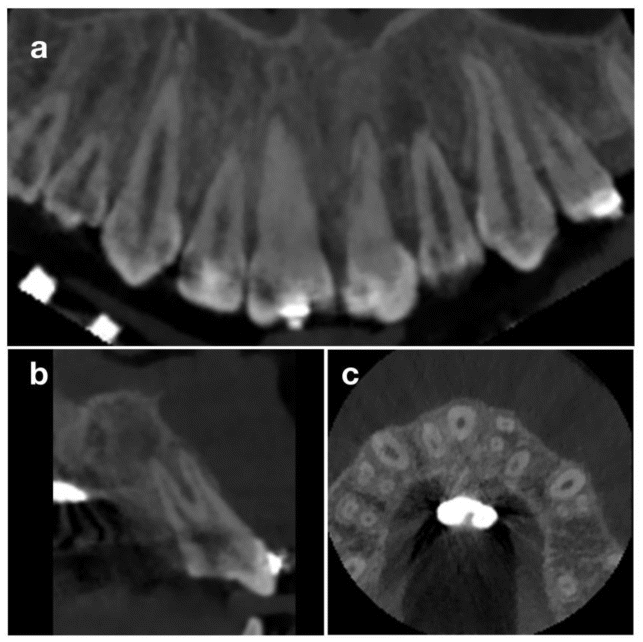

Thermal sensitivity testing confirmed vitality in all adjacent teeth except 2.1. Periapical radiography demonstrated an incongruent root canal treatment, incomplete root development, and a periapical radiolucency (Figure 1b). A preliminary plan of nonsurgical endodontic retreatment was considered; however, upon re-entry, methylene blue staining revealed a vertical distal root fracture (Figure 1c). CBCT confirmed a vertical fracture of 2.1 and a large osteolytic lesion extending to 2.2, with complete loss of the interdental septum and vestibular alveolar fenestration (Figure 2).